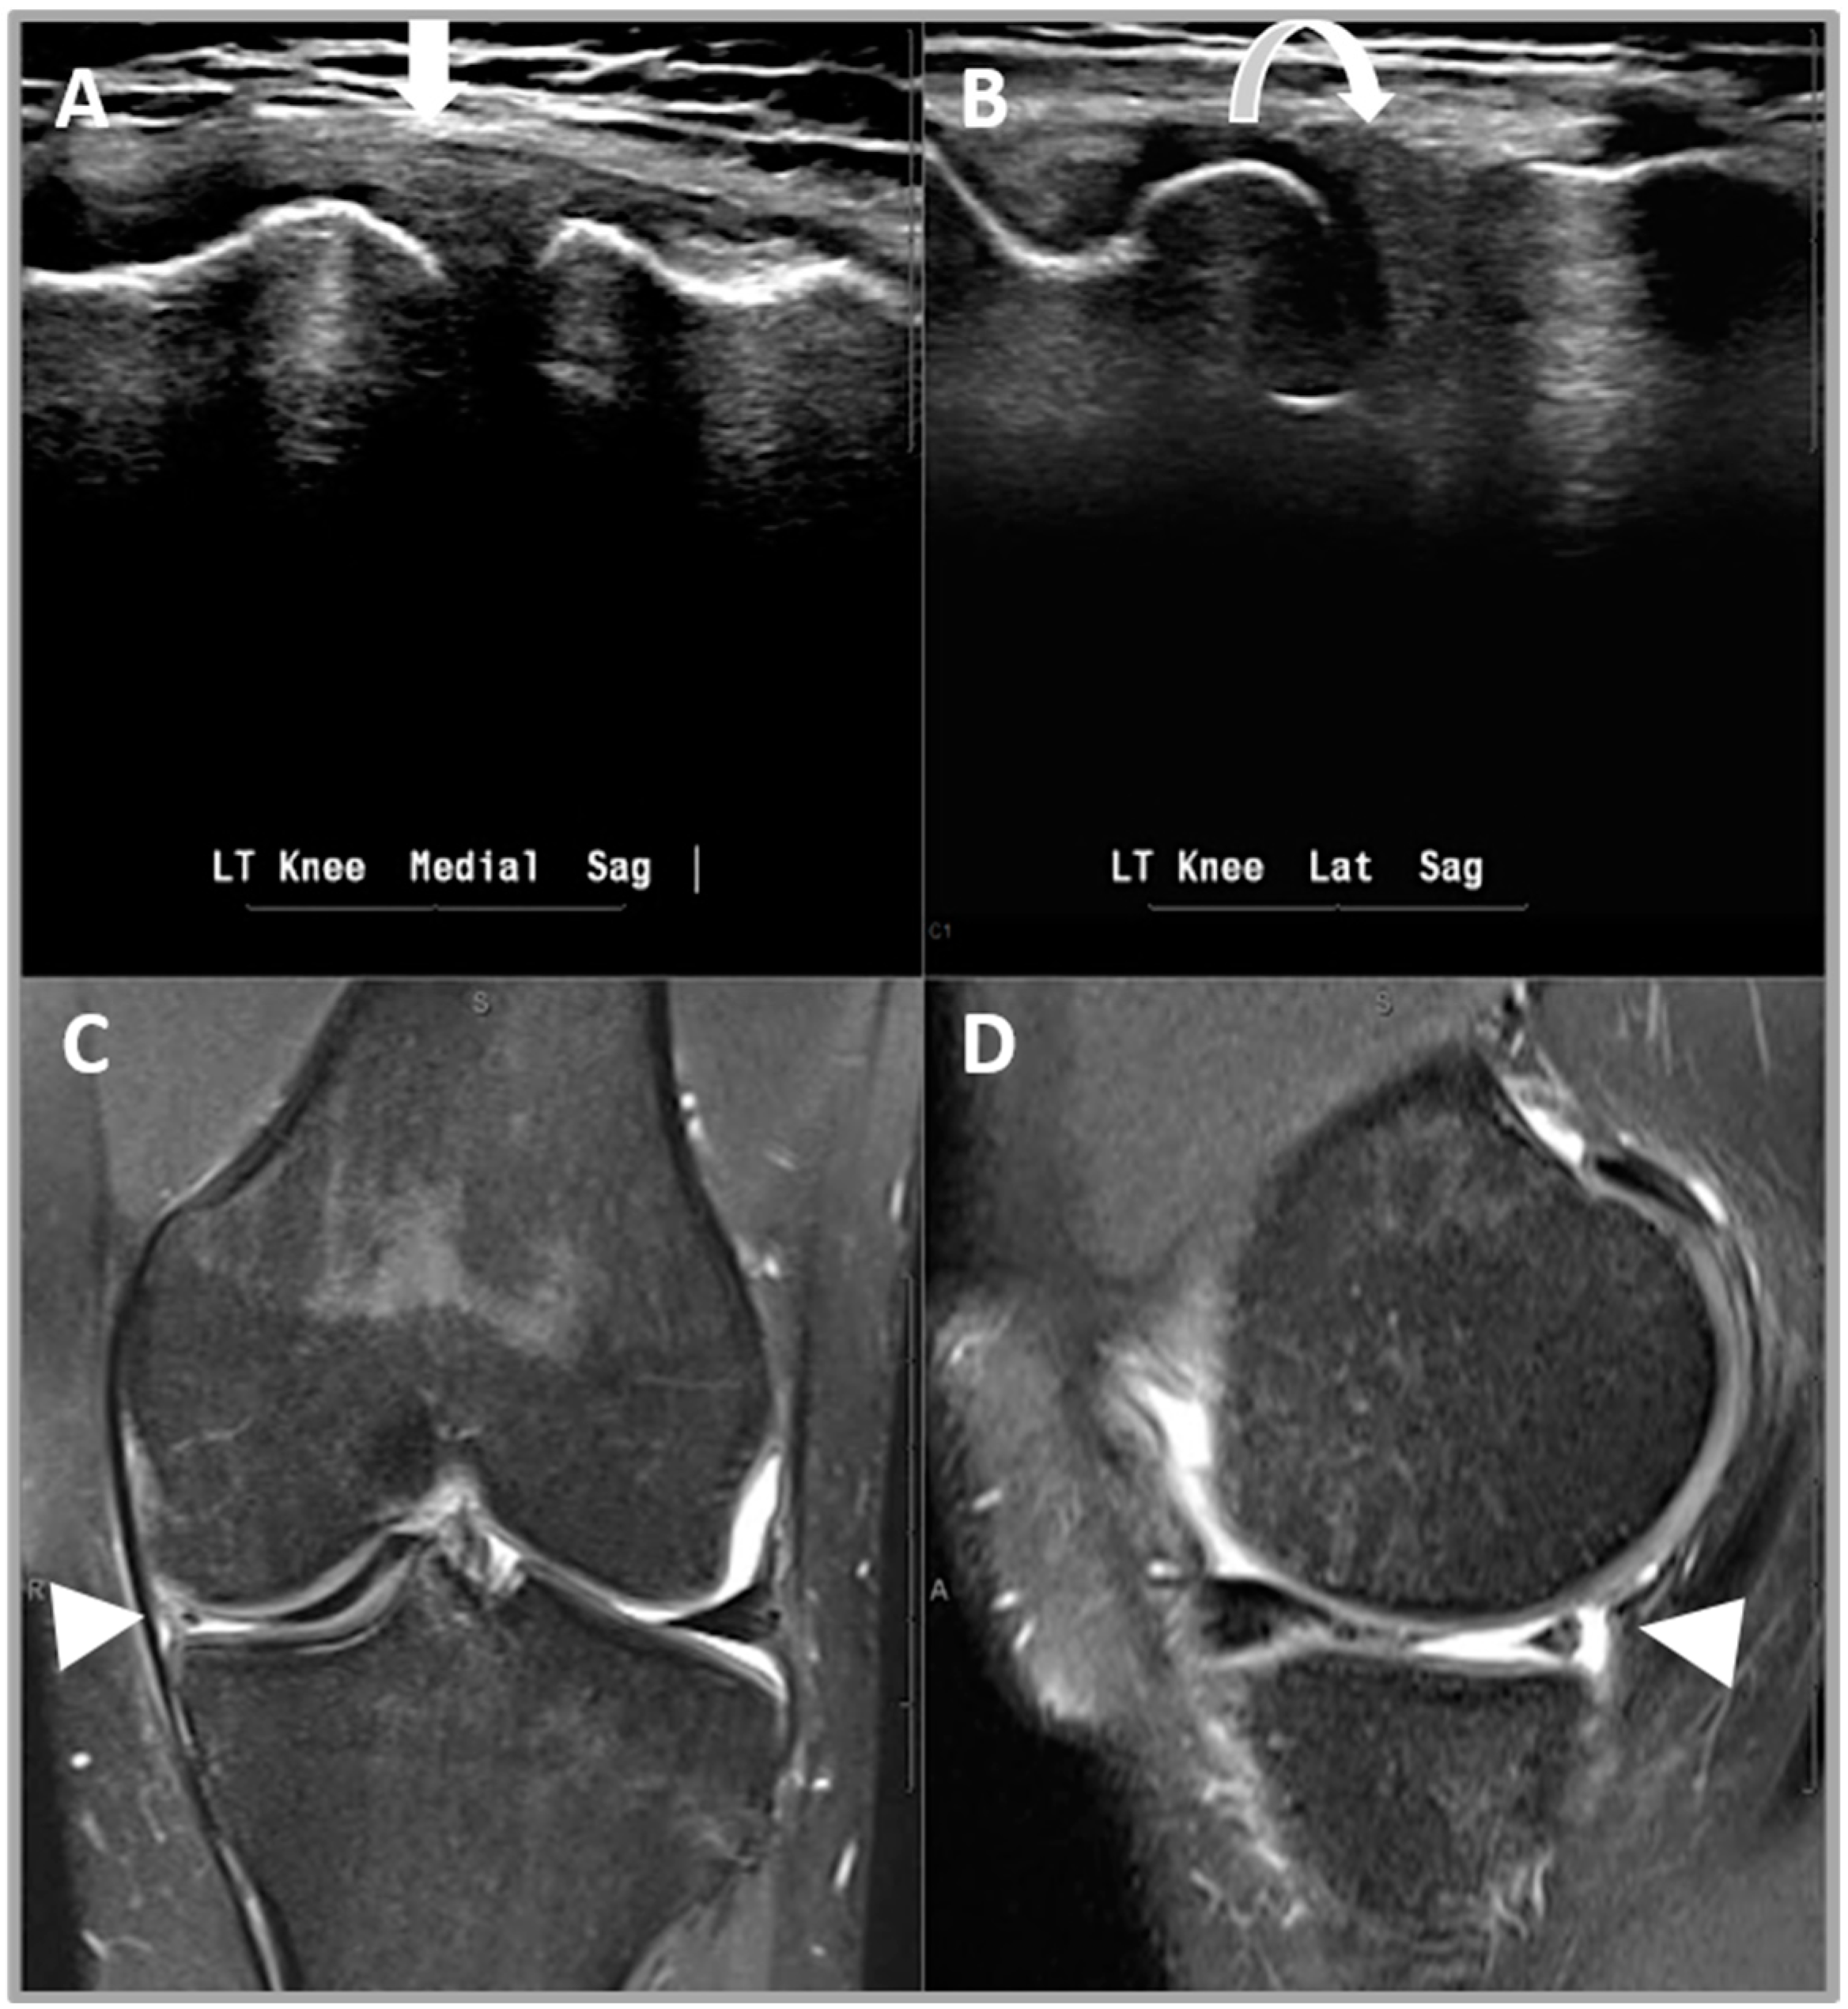

2.5.4. Criterion 4—Displaced Meniscal Fragment

2.5.5. Criterion 5—Extruded Meniscus